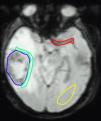

Material y métodosSe aplicaron 2 modelos de perfusión por RM, monocompartimental y farmacocinético, en 15 pacientes diagnosticados de astrocitoma grado IV. Con el modelo monocompartimental se cuantificó el volumen sanguíneo cerebral (VSC), el tiempo de tránsito medio (TTM) y el flujo sanguíneo cerebral (FSC). Con el farmacocinético se midió la constante de permeabilidad (Ktrans), el coeficiente de extracción (kep), la fracción de volumen del espacio intersticial (ve), la fracción de volumen vascular (vp), la permeabilidad en primer paso (Kfp) y el volumen vascular en primer paso (vpfp). Para cada parámetro se obtuvieron los histogramas del área tumoral total, peritumoral y sana. El análisis estadístico incluyó un análisis de varianza para cada parámetro y un análisis discriminante.

ResultadosLas diferencias más significativas entre las regiones se obtuvieron con el VSC, FSC, Ktrans y vpfp, siendo VSC el que mostró mejores resultados. La mejor función clasificatoria mediante análisis discriminante se obtuvo para una combinación de Ktrans y VSC. El análisis de la forma del histograma evidenció diferencias estadísticamente significativas para la curtosis de Ktrans y kep, así como para la asimetría de VSC, FSC, Ktrans y vpfp.

ConclusiónEl VSC es el parámetro que aisladamente permitió diferenciar mejor entre área tumoral, peritumoral y sana. La función clasificatoria generada a partir de VSC y Ktrans consiguió mejorar estos resultados haciendo más eficaz la clasificación por áreas.

Material and methodsWe applied two models of MRI perfusion, the unicompartmental and the pharmacokinetic models, in 15 patients diagnosed with grade IV astrocytoma. In the unicompartmental model, we quantified cerebral blood volume (CBV), mean transit time (MTT), and cerebral blood flow (CBF). In the pharmacokinetic model, we measured the permeability constant (Ktrans), the extraction coefficient (kep), the fraction of the volume in the interstitial space (ve), the fraction of the volume in the vessels (vp), the permeability in the first pass (Kfp), and the vascular volume in the first pass (vpfp). For each parameter, histograms were obtained for the total tumor area, for the peritumoral area, and for the healthy tissue. The statistical analysis included an analysis of variance for each parameter and a discriminant analysis.

ResultsThe most significant differences between the regions were obtained with CBV, CBF, Ktrans, and vpfp; of these, CBV had the best results. The best classificatory function on the discriminant analysis was the combination of Ktrans and CBV. The analysis of the shape of the histogram showed statistically significant differences for the kurtosis of Ktrans and kep, as well as for the skewness of CBV, CBF, Ktrans, and vpfp.

ConclusionWhen parameters are considered individually, CBV is the one that best enables differentiation between tumor, peritumoral, and healthy tissue. The classificatory function generated from CBV and Ktrans results in improved classification by areas.